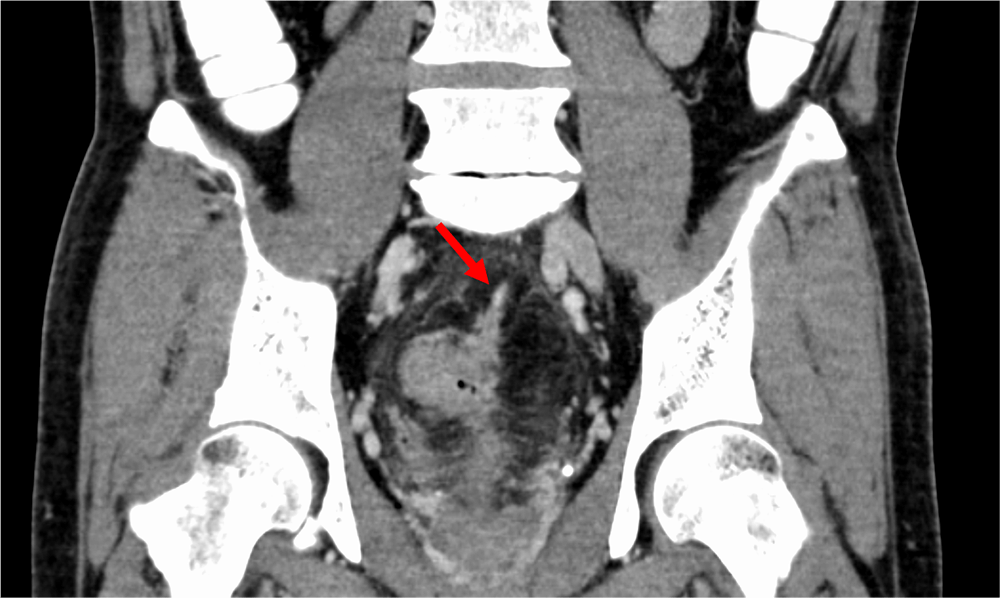

図3.門脈相(120kVp画像)、冠状断

下腸間膜静脈(矢印)に連続するような、EMVIを認める。

また直腸癌の予後不良因子である壁外静脈浸潤(EMVI)、tumor deposit(TD) の同定は重要であることが知られている。これらはMRIで診断されることが一般的であるが、造影CT検査でも指摘できることがある。仮想単色X線エネルギー画像(MonoE)は低エネルギー帯でヨードの造影効果が劇的に増加するため、病変や脈管の視認性が向上するので、検出能や診断確信度の向上に寄与すると考えられる。